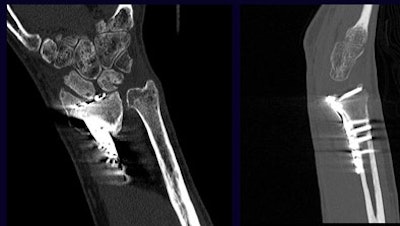

To maximize resolution, Gold's group follows the so-called "3-1-0.5" rule for its MDCT scans, meaning that maximum collimation is set at 3 mm in large sections such as the pelvis and shoulder girdle, 1 mm at the elbow and knee, and 0.5 mm for hand, wrist, and foot imaging.

| For MDCT the traditional 3-2-1 rule is modified to 3-1-0.5, meaning that maximum collimation is set at 3 mm in large bones such as the pelvis and shoulder girdle, 1 mm for elbows and knees, and 0.5 mm for hands, wrists, and feet. All images courtesy of Dr. Garry Gold. |

"It used to be the 3-2-1 rule, but the technology keeps improving," Gold said in a presentation at the 2005 International Symposium on Multidetector-row CT in San Francisco. And beyond thinner slices, kVp and mAs should be adjusted upward, pitch reduced to less than 1, and scan orientation adjusted to minimize the x-rays hitting the metal, he said.